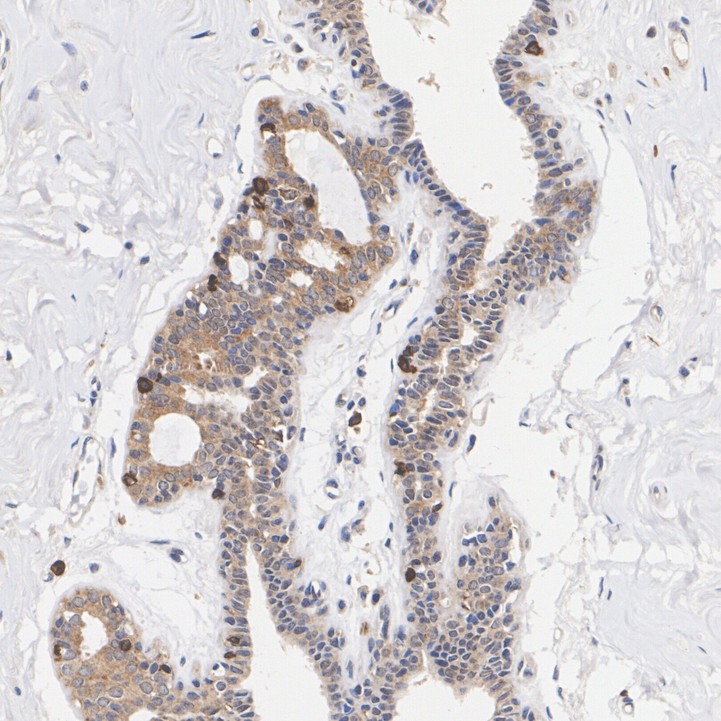

Immunohistochemical analysis of paraffin-embedded human breast tissue with Rabbit anti-Phospho-GSK3 alpha (S21) antibody (HA723069) at 1/200 dilution.

The section was pre-treated using heat mediated antigen retrieval with Tris-EDTA buffer (pH 9.0) for 20 minutes. The tissues were blocked in 1% BSA for 20 minutes at room temperature, washed with ddH2O and PBS, and then probed with the primary antibody (HA723069) at 1/200 dilution for 1 hour at room temperature. The detection was performed using an HRP conjugated compact polymer system. DAB was used as the chromogen. Tissues were counterstained with hematoxylin and mounted with DPX.